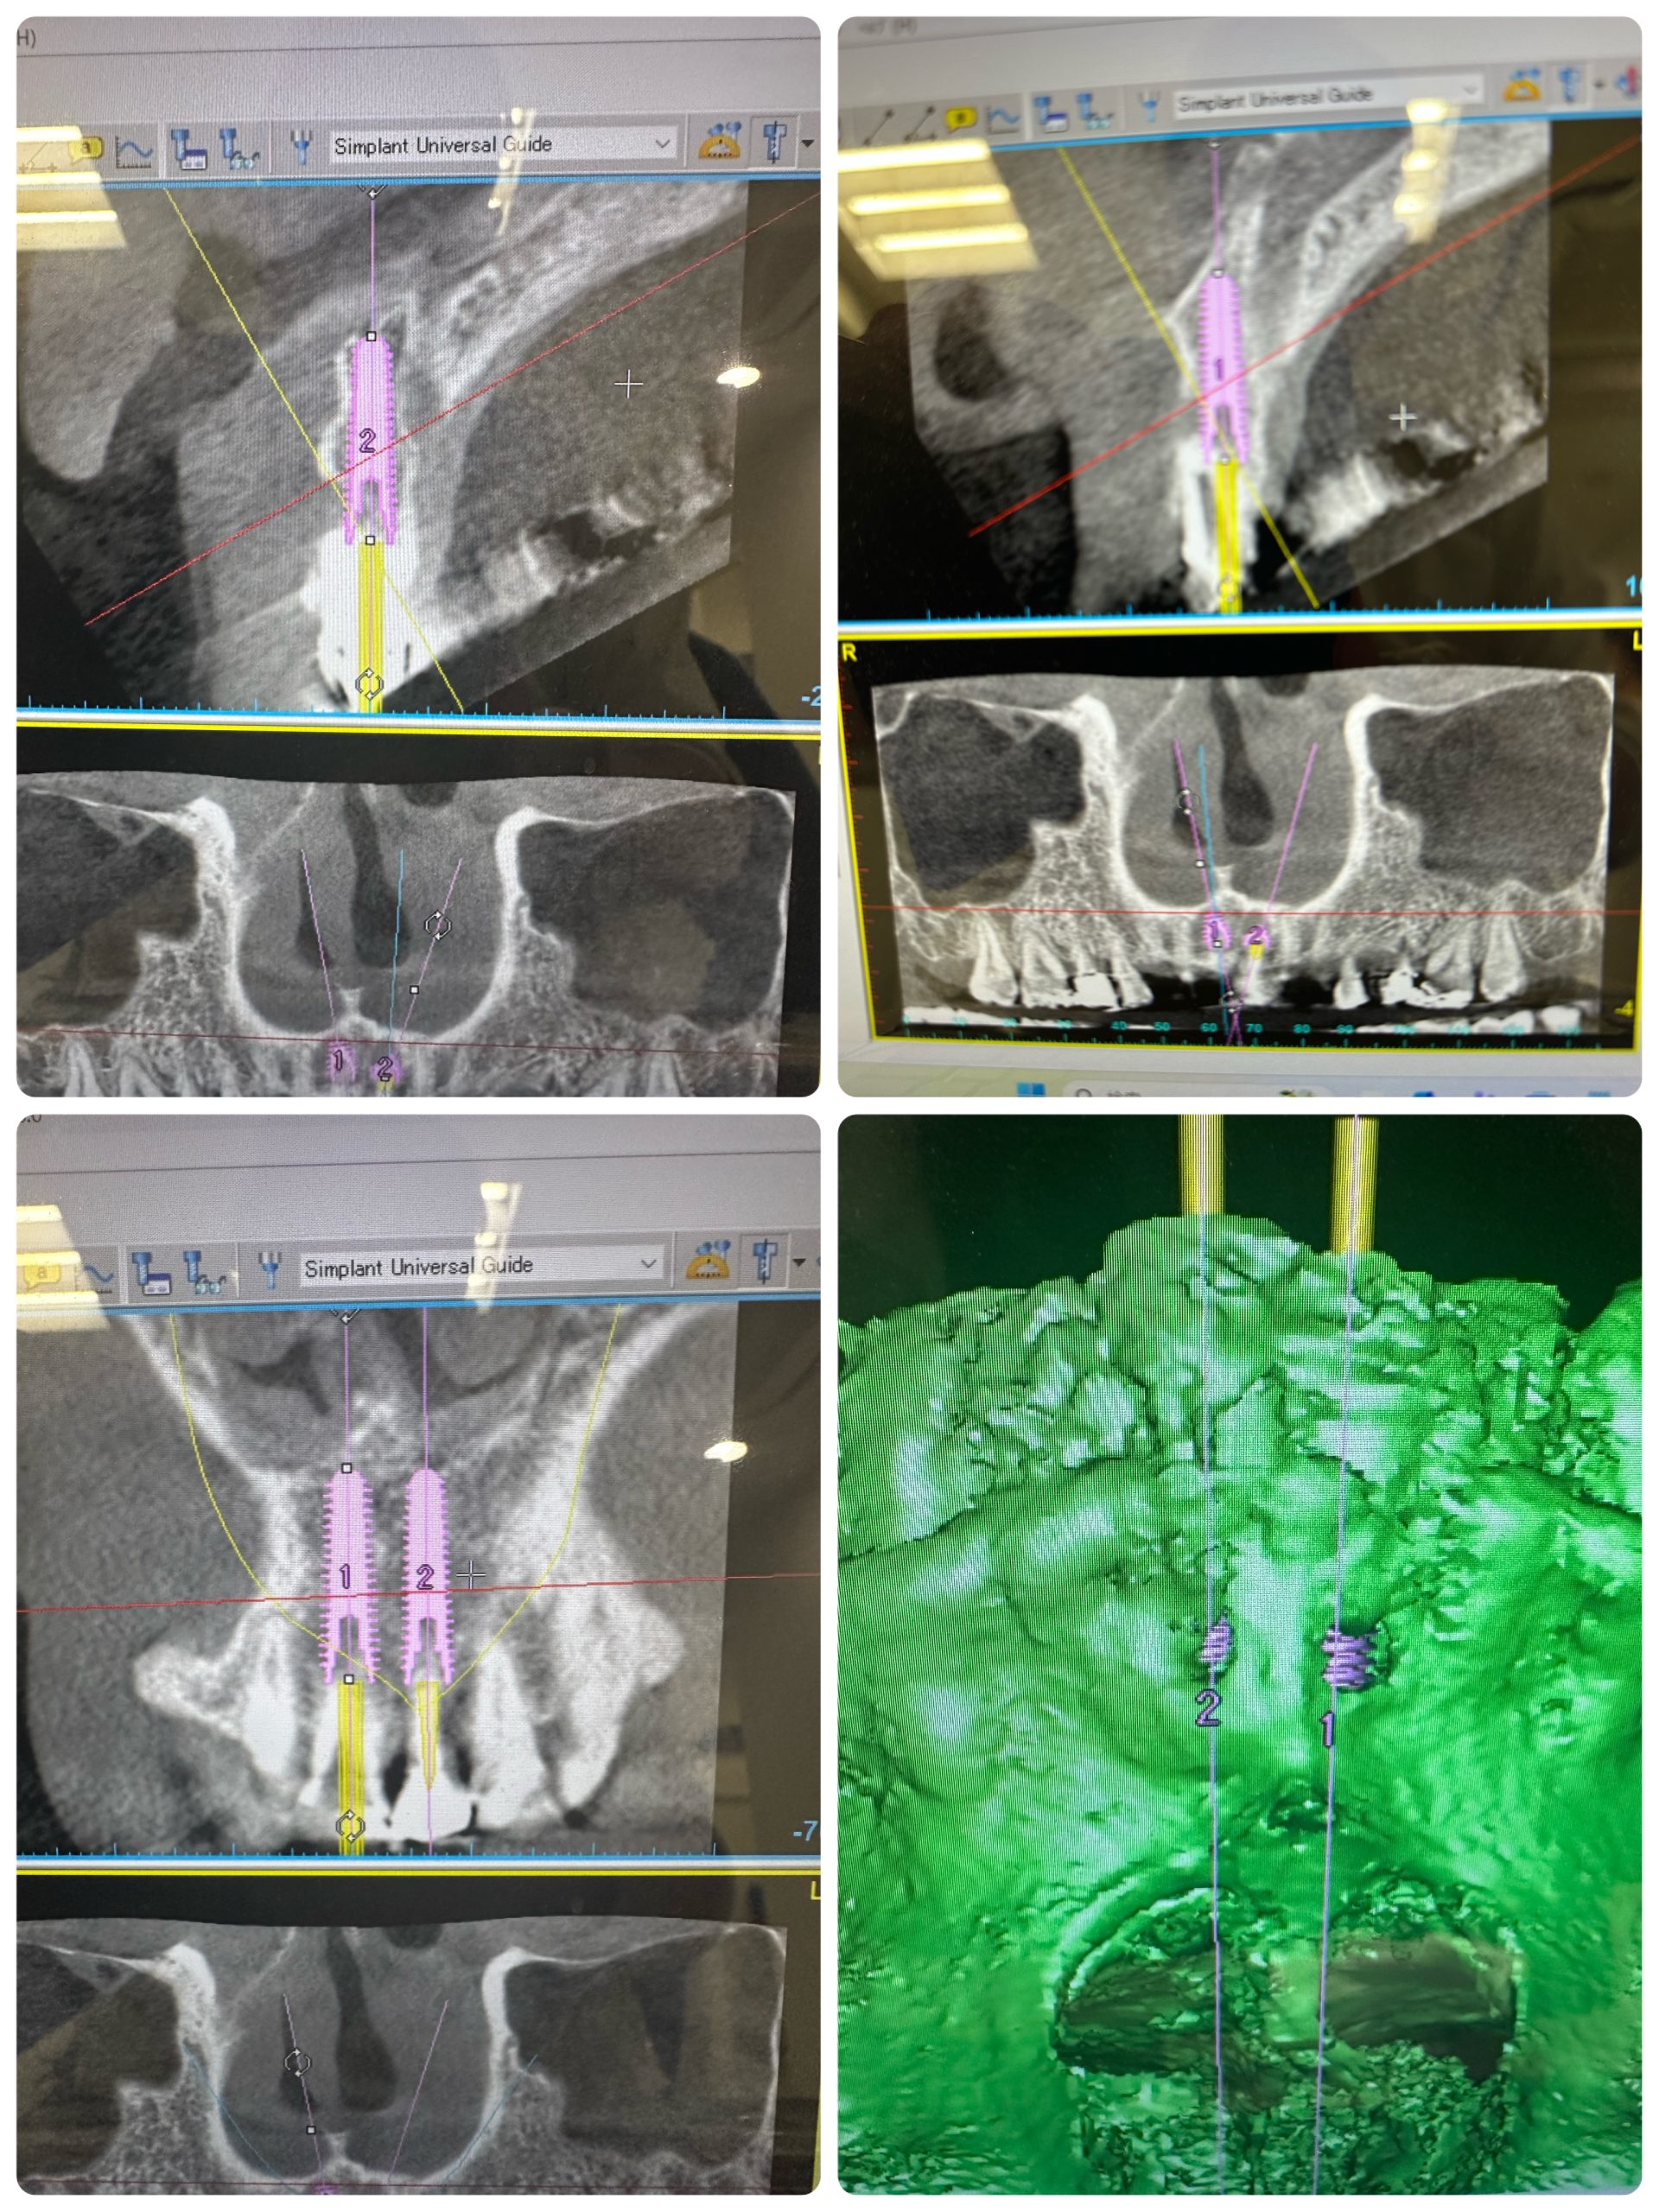

新大久保歯科医院